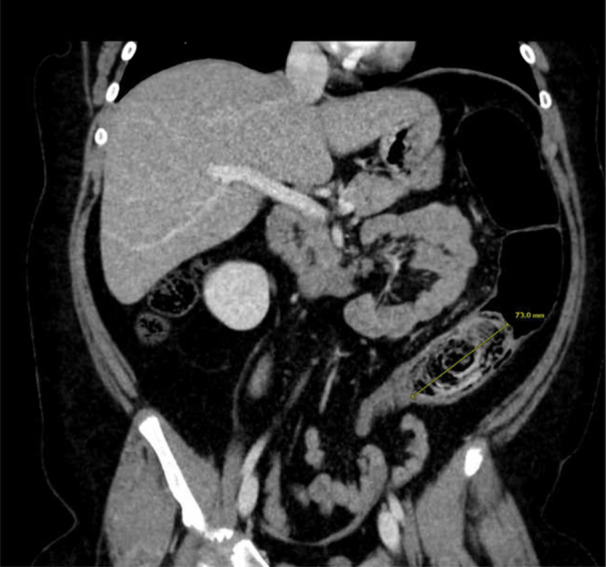

Gastric bezoars and small bowel bezoars are uncommon in the pediatric population, and colonic bezoars are even rarer. We present the case of a 9-year-old female who presented with acute abdominal obstruction symptoms and a diagnosis of colonic phytobezoar. The phytobezoar was removed via endoscopic intervention. This case is important as it demonstrates that colonic bezoars can occur in children, may not be amenable to oral laxative or enema therapy, and may require endoscopic removal.